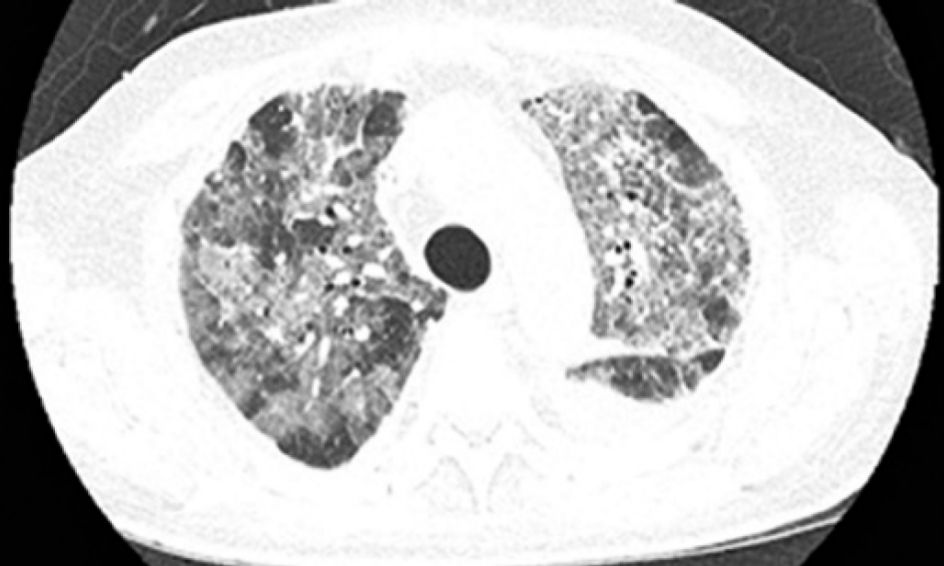

患者是一名69岁的老年男性,身患晚期转移性结肠癌,肿瘤已经转移到了肝、肺和骨组织。患者曾接受了氟嘧啶、铂、抗血管生成药、伊立替康和西妥昔单抗,但是不幸的是,所有治疗最终都没能改变病人的情况,肿瘤病情一直在持续不断的恶化,考虑到病人的实际情况,患者开始接受帕博利珠单抗(Pembrolizumabe)的治疗,每两周10mg/Kg,在第二次治疗之后,病人开始出现了发热和呼吸困难。体格检查显示,病人的血氧饱和度仅为83%,CT检查显示其左肺出现间质性肺炎,双侧胸腔都存在积液,血细胞计数显示病人的白细胞增多。为了控制肺部症状,患者在行胸腔穿刺术后,又使用了头孢曲松+克拉霉素,但是病情却并没有出现好转。CT复查显示病人的病情并没有因抗生素的使用而出现好转,反而进一步加重,双肺磨玻璃影进一步扩大。

患者是一名81岁的老年男性,身患ⅢA期难治性肺腺癌。病人在进行手术治疗后又接受了放疗和卡铂+培美曲塞的辅助化疗。在随访4个月后,病人的病情出现了局部复发,在放疗治疗无效后,病人又接受了卡铂和紫杉醇的姑息性化疗,但是其病情并未得到有效的控制。同样,病人在传统治疗无效后选择了帕博利珠单抗每3周2mg/kg的免疫治疗方案。在治疗4个疗程后,病人开始出现呼吸困难和干咳,血氧饱和度也降至80%。CT检查显示双侧肺部出现弥漫性浸润灶,血常规检查显示其白细胞计数增高。所幸的是,病人在对症使用甲基强的松龙2mg/kg和抗生素治疗后,其肺部炎症得到了比较好的控制。

患者是一名54岁的老年男性,被确诊为肺大细胞神经内分泌癌,并且已经出现了转移。最初,病人使用了卡铂和紫杉醇进行治疗,随后又使用了顺铂和依托泊苷,同时接受了定向放疗。但是传统治疗的疗效并不理想,病人很快出现了中枢神经系统和肝脏的转移,因此帕博利珠单抗每3周2mg/kg的治疗方案再次临危上阵。在治疗5个疗程后,病人开始出现呼吸困难和咳嗽(无发热),氧饱和度仅为84%,CT检查显示其双肺出现了磨玻璃样变性。因此,病人开始每6小时使用哌拉西林-他唑巴坦4.5g的甲羟泼尼松2mg/kg进行治疗,在治疗开始后的24小时内,病人的肺部病情就出现了好转,治疗1周后的CT检查显示,病人肺部原先的浑浊阴影几乎全部消失。

该患者是一名70岁的老年男性,患有转移性肺表皮样癌合并多发性肝损伤。因患者的基本状态并不适用于铂类化疗,因此病人直接使用了纳武利尤单抗(Nivolumab)每2周3mg/kg进行治疗。在治疗4个疗程后,病人开始出现精神混乱、呼吸困难和干咳等症状(无发热),其血氧饱和度也跌到了74%,血细胞计数正常。CT检查显示其肺部出现了磨玻璃样浸润区。因考虑患者可能出现了免疫相关性的肺炎,其开始接受甲基强的松龙每8小时60mg的治疗,抗生素治疗也同步进行。仅仅在数小时内,患者的病情就出现了好转,并在治疗3天后就完全治愈出院。

在本次报道的5名病人中,仅有一人为5级不良反应,并最终去世。其他4名病人均为3级不良反应,在接受糖皮质激素治疗后病情都有改善。大多数病人的CT表现肺部的磨玻璃样改变,早期临床表现为咳嗽和呼吸困难,不论对于病人还是医务工作者来说,免疫性肺炎的早诊断和早治疗都尤为重要,以上报道的病人中,有几人就是因为早诊断早治疗,在很短的时间内肺炎症状就得到了快速的缓解,因此我们说:肺炎不可怕,“早”字是关键。